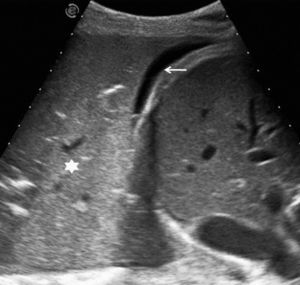

En pacientes de difícil movilización, como los ingresados en unidades de cuidados intensivos, la ecografía también es útil para determinar si las alteraciones visibles en la radiografía anteroposterior en decúbito supino corresponden a derrame pleural o a consolidaciones parenquimatosas (fig. 2). Además, como se comenta más adelante, también permite la obtención de líquido pleural de forma rápida y segura.